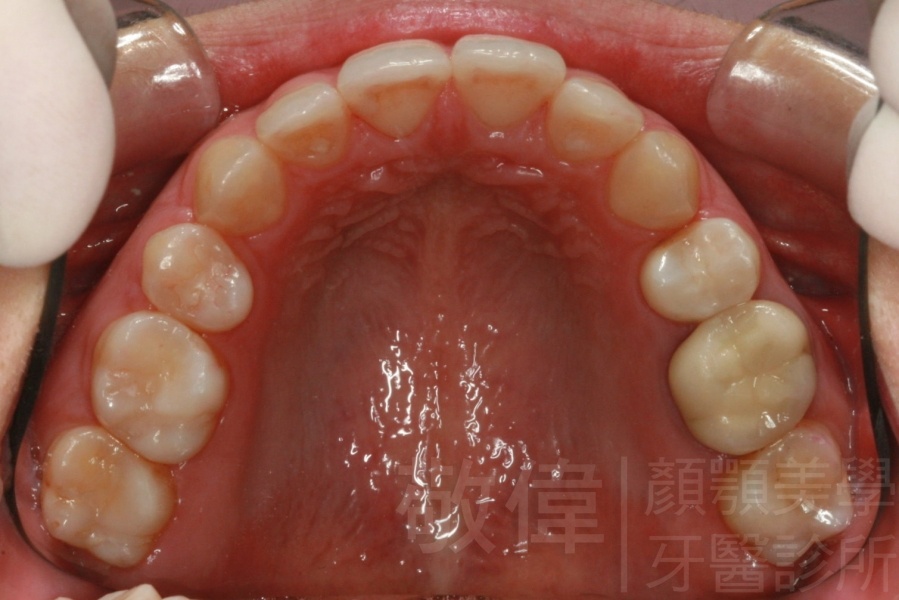

齒顏矯正/戽斗臉型 變身 大帥哥

矯正前-上   矯正前-下

矯正後-上   矯正後-下

<個案說明>

戽斗(學名第三級咬合 class III)矯正之後,戽斗的樣子就比較沒有了。最主要的改變是在牙齒的咬合。從側面比較,治療前、治療後的臉型 可更明顯看出來 戽斗的感覺 減少了很多。